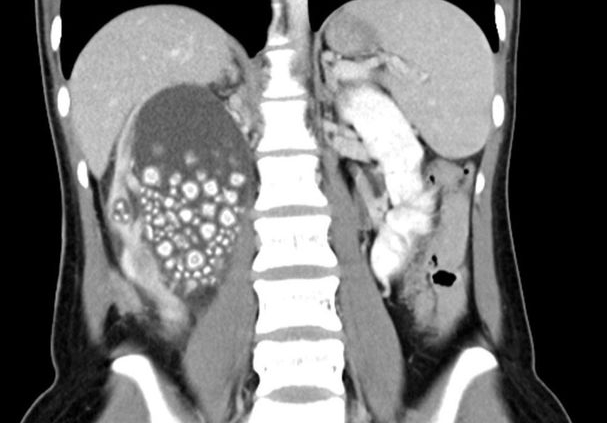

پس از بررسیهای اولیه، پزشکان متوجه شدند که کلیه راست زن به شدت متورم است و برای تشخیص علت، از او اسکن اشعه ایکس گرفتند. آنها با دیدن کلیه این زن که با بیش از ۳۰۰ سنگ بین ۰.۵ تا ۲ سانتیمتری پر شده بود متحیر شدند.

پس از یک عمل جراحی دو ساعته به نام نفرولیتوتومی از راه پوست (سنگ شکن از راه پوست)، پزشکان مقدار زیادی از سنگها را از کلیه او خارج کردند که به گفته دکتر لین کاییانگ، جراح، شبیه نانهای حجیم پختهشده بودند.

تصویر منتشر شده از سنگهای خارج شده از کلیه این زن در شبکههای اجتماعی باعث تعجب فراوان کاربران شد.